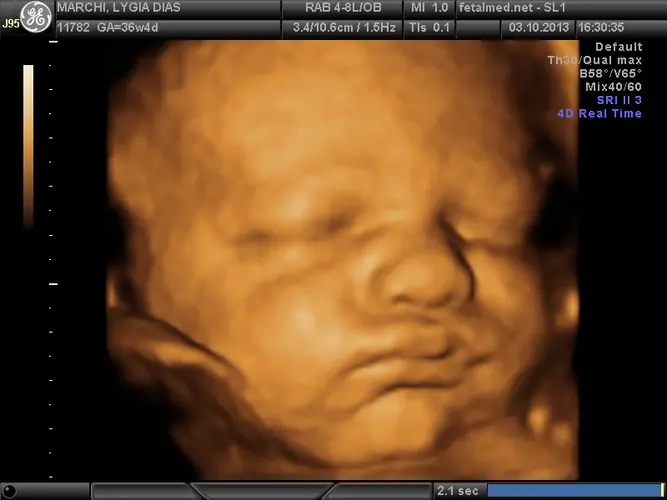

Seu bebê está praticamente pronto para nascer! Com cerca de 2,7 quilos e medindo entre 45 e 48 centímetros, ele já atingiu um tamanho considerável e seus sistemas estão funcionando de forma coordenada. A maioria dos órgãos, incluindo os sistemas circulatório e músculo-esquelético, está preparada para a vida fora do útero.

Nesta semana, a gordura continua se acumulando, especialmente preenchendo os ombros e joelhos do bebê, além de formar dobrinhas características no pescoço e na cintura. Essas reservas de gordura são fundamentais para regular a temperatura corporal após o nascimento. As gengivas estão endurecendo progressivamente, preparando-se para a futura erupção dos primeiros dentinhos.

O espaço uterino está cada vez mais apertado, e se o bebê ainda não se posicionou de cabeça para baixo (posição cefálica), as chances de ele conseguir se virar diminuem significativamente. A partir desta semana, ele pode “encaixar” no canal de parto a qualquer momento, iniciando sua descida em direção à pelve materna.